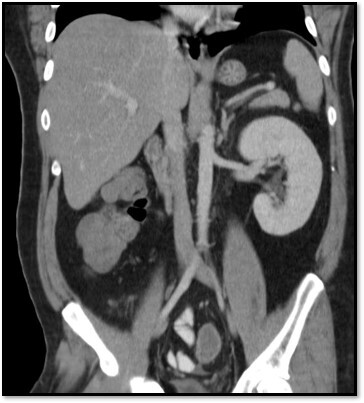

What pathology is seen here?

Polycystic Kidney Disease